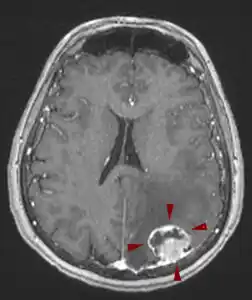

Ο μεταστατικός (δευτεροπαθής) όγκος εγκεφάλου ξεκινάει ως καρκίνος σε κάποιο άλλο σημείο του σώματος και διασπείρεται στον εγκέφαλο. Οι μεταστατικοί όγκοι του εγκεφάλου, θεωρούνται στο σύνολό τους κακοήθεις.

egkefaliki metastasi melanoma 252x300Οι κύριες θεραπείες για τους μεταστατικούς όγκους του εγκεφάλου είναι: